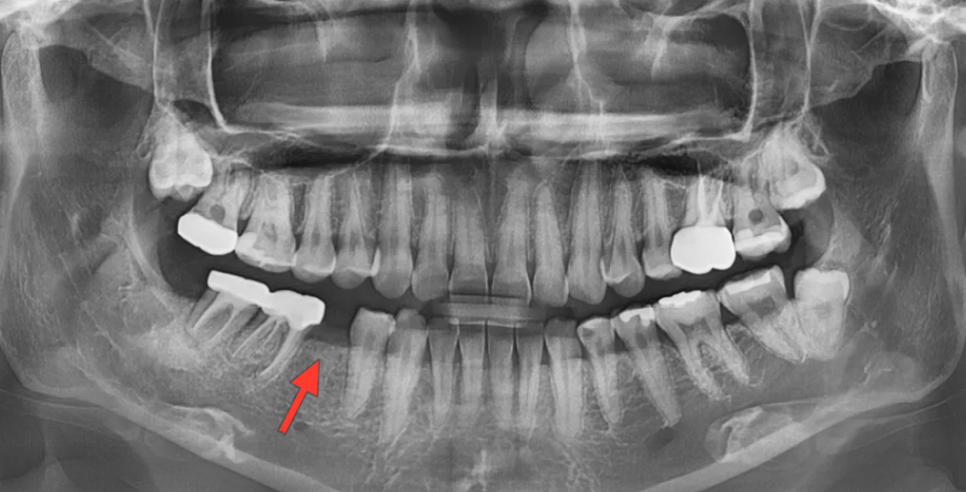

초진 검사 – 파노라마 및 안모 분석

치료를 시작하기 전, 먼저 파노라마 엑스레이와 안모(얼굴) 사진을 촬영하여 전반적인 구강 상태와 얼굴 비율을 분석했습니다.

오른쪽 아래 두 번째 작은어금니가 없으셨음

환자분은 오른쪽 아래 두번째 작은어금니가 빠져 있는 상태였고, 왼쪽 아래 두번째 작은어금니에는 인레이가 수복되어 있었습니다. 그 외에도 왼쪽 위 첫번째 큰어금니, 오른쪽 아래 첫번째·두번째 큰어금니에 신경치료 후 크라운이 씌워져 있었고, 양쪽 위·아래로 매복 사랑니가 확인되었습니다.